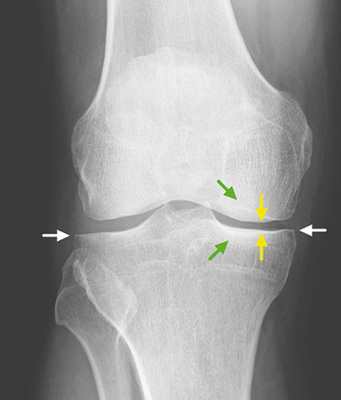

Konsensusempfehlung BK 2112 Merkmal „definiter“ Osteophyt

Ein definiter Osteophyt ist eine knöcherne Ausziehung einer Größe 2 mm ab antizipierter Knochenform des Gelenkrands (  Abb. 5 , Beispiele auch Nagaosa et al. 2000; Altman u. Gold 2007). Patellär sind nur die seitlichen Anbauten als relevant zu werten. Hier ist darauf zu achten, diese nicht mit Sehnenansatzverkalkungen oder Fibroostosen zu verwechseln (Freyschmidt et al. 1978).

Konsensusempfehlung BK 2112 Gelenkspalt-verschmälerung

Basierend auf Normwerte nach Lanyon (1998), der Gelenkspaltmessungen an 86 Frauen und 39 Männern ohne Kniebeschwerden und ohne Osteophyten durchgeführt hatte (Altersverteilung 40–75 Jahre, Durchschnittsalter 58 Jahre), einigte sich die Konsensusgruppe auf folgende Werte für eine vorliegende Gelenkspaltverschmälerung: siehe   Tabelle 2 für das Femorotibialgelenk und   Tabelle 3 für das Patellofemoralgelenk.

Sonderfall „definitive“ Gelenkspaltverschmälerung ohne Osteophyten

Die Kellgren-Lawrence-Skala wird seit jeher kontrovers diskutiert, da sie einen starken Fokus auf osteophytäre Anbauten legt. Dadurch wird die atrophe Form der Arthrose (  Abb. 6 ), bei der es zur Gelenkspaltverschmälerung ohne wesentliche Osteophyten kommt, vernachlässig und kann nicht klar eingestuft werden. Hierfür schlägt die Konsensusarbeitsgruppe BK 2112 (2014) vor, dass diese analog zu Kellgren-Lawrence-Grad 3 oder 4, Letztere wenn eine starke Verschmälerung und definitive Verformungen des Femurs und der Tibia vorliegen, einzustufen.